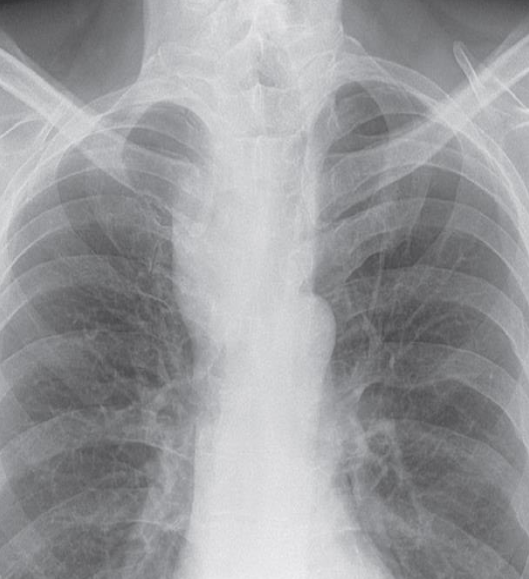

RESPIRATORY AND CARDIOVASCULAR RADIOPLOGY

A. What is the most likely diagnosis in the given images; RT lower lobe pneumonia

B. Which lobe of the lung affected by this disease in the given image. Lower lobe, reverse change of opacity from spine

A. What is the most likely diagnosis in the given images

pneumonia ex… due fever cough and the imaging

B. Which lobe of the lung affected by this disease in the given image. Right middle Lobe Lesion, due obliteration of diaphragm - and lateral of horizontal fissure opaque

Pneumonia most common due to no deviations of midline - could be truama, ectopy, etc… so follow through with case given for diagnosis